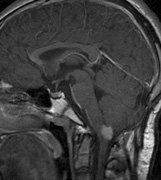

Optic nerve gliomas may involve the optic chiasm and be associated with endocrine disorders or nystagmus.68–70 Surgical excision of chiasmal gliomas (Fig. 6) carries a high risk of visual loss. Invasion of the hypothalamus or the third ventricle carries a poor prognosis, with greater than 50% 15-year mortality rate.71 One review of radiation treatment for chiasmal gliomas collated data from small case series and found no significant long-term improvement in visual function, progression, or mortality with radiation treatment.71 Other reports suggest that radiation doses over 4500cGy improve symptoms and slow progression of chiasmal gliomas over several years.72 Adequate tumor coverage by radiotherapy results in irradiation of normal brain and nearly all children need hormone replacement.73 Chemotherapy is an alternative.74,75

Fig. 6. Surveillance images of a 12-year-old girl with NF1 and an optic nerve glioma which has extended to involve the chiasm. Pre- (a) and postcontrast (b) T1-weighted coronal images reveal a large suprasellar mass with an enhancing component (arrow) seen separately from the normally enhancing pituitary gland. (c) Axial scans through the suprasellar cistern show the tumor is high signal on T2-weighted scans. (d) Enlargement of the chiasm, optic nerve and hypothalamus is visible on the post-contrast T1-weighted sagittal image. Although optic nerve glioma usually has a good prognosis (with visual function often remaining stable in the absence of any intervention66,67), chiasmal involvment is a poor prognostic indicator. A sign of chiasmal involvment may be new onset of endocrine disorders or nystagmus. Surgical excision of chiasmal gliomas carries a high risk of visual loss.68–70